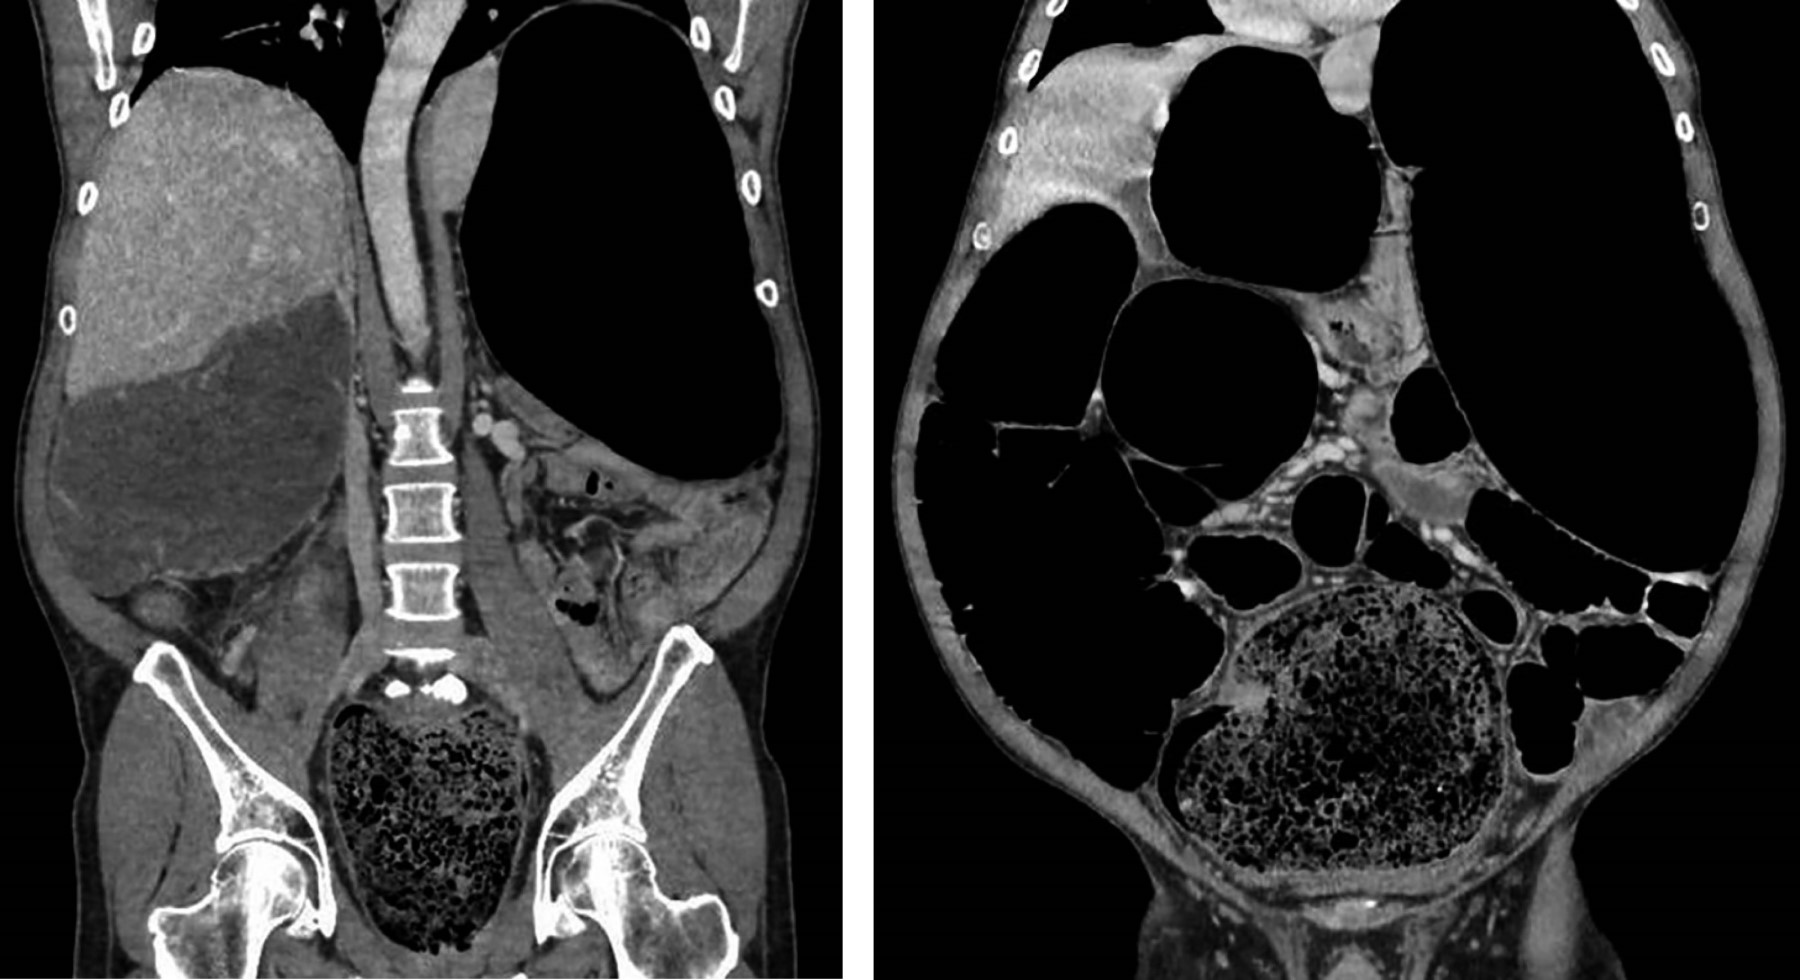

En la primera gasometría resulta llamativa la escasa afectación del equilibrio ácido-base (pH 7.4, PCO2 40.4 mmHg, CO3H- 28.3 mEq/L) e iónico (K+ 3.4, Na++ 135, Ca++ 1.10, Cl- 97), aunque presenta hemoglobina 16.4 g/dL y lactato 3.8 mmol/L. La analítica muestra 520,000 plaquetas/µL, sin afectación renal (urea 51 mg/dL, creatinina 1.16 mg/dL) ni trastornos de la coagulación (INR [International Normalized Ratio] 1.16, TTPAratio [Tiempo De Tromboplastina Parcial Activado-Relación] 1.11). La tomografía axial computarizada (TAC) muestra un gran fecaloma en ampolla rectal que provoca dilatación significativa colorrectal (16 cm en colon transverso y 13 cm en ciego) de íleon y yeyuno distal (Figuras 2 y 3). El estómago e intestino delgado proximal están colapsados y no existe neumoperitoneo ni líquido libre intraabdominal.

Figura 2

Figura 3